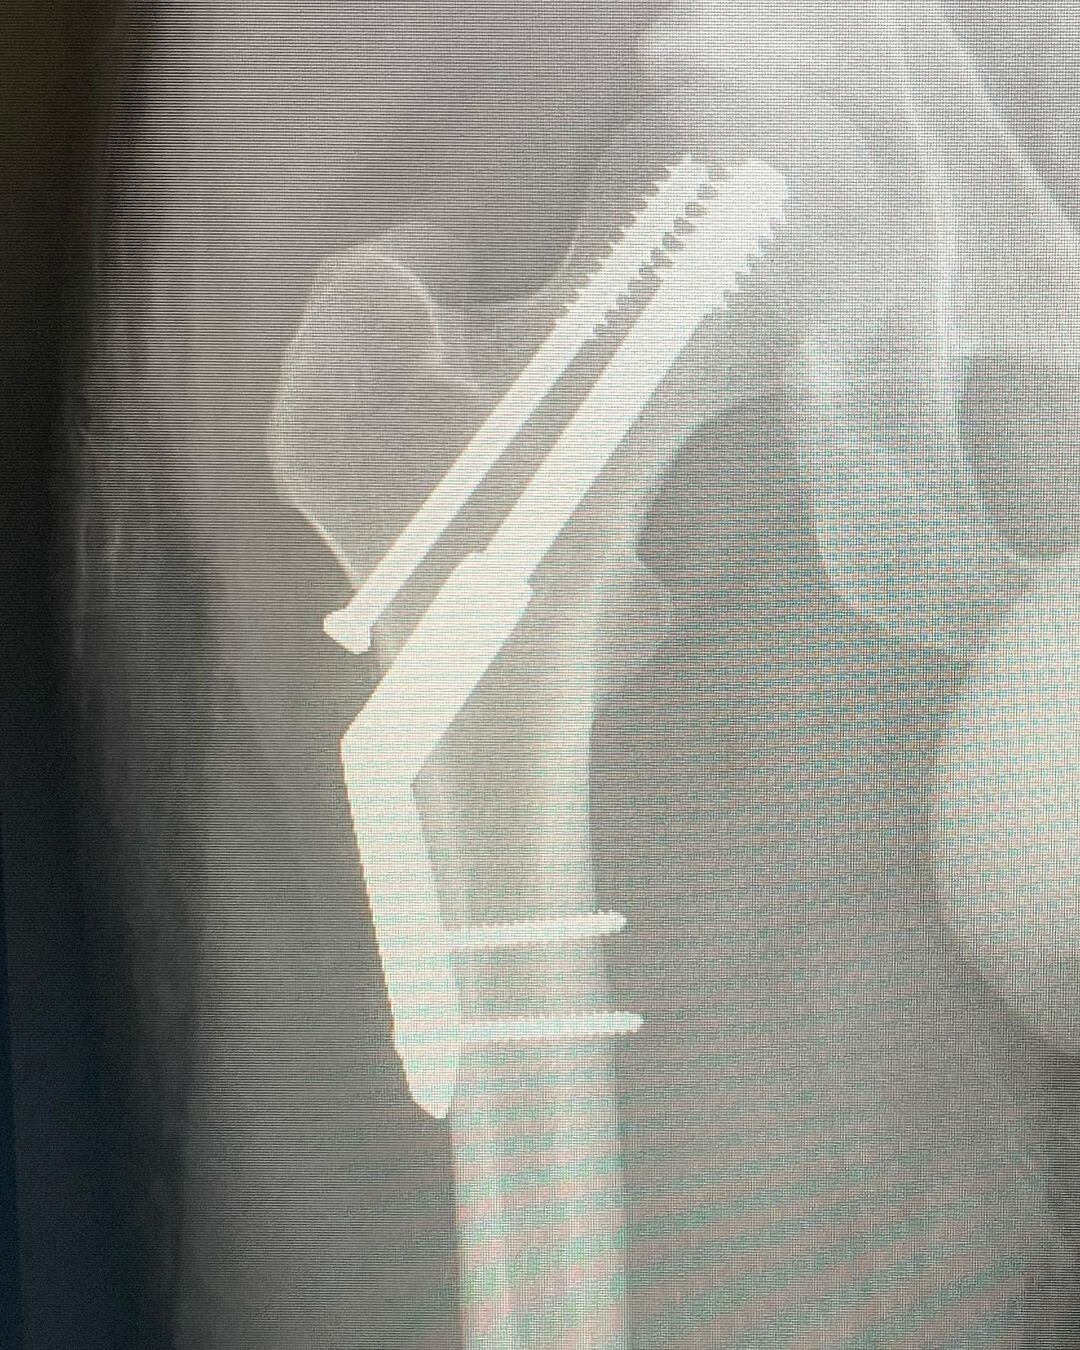

“Me fracturé la cadera. Traté de correr una media maratón en lo que resultó ser una fractura por estrés existente. Ups. Llegué a menos de 1 km de la línea de meta. Así es la vida, supongo. Todos los espectáculos en México y Sudamérica van adelante como lo planeado, no voy a renunciar a ustedes chicos ❤️”, posteó el artista.

Fuente: Instagram/ @Tameimapala